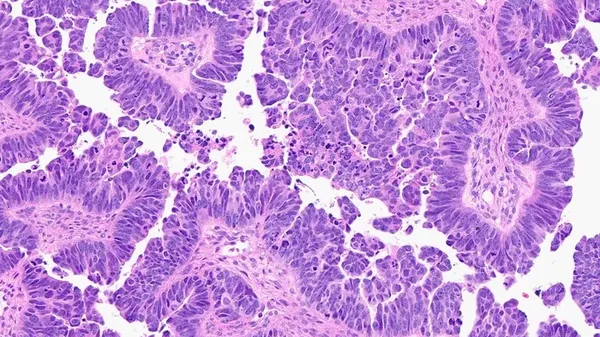

La fibrosi cistica fa sentire il suo peso anche sull ’età biologica dell’organismo, facendolo invecchiare di tre-quattro anni , ma è anche possibile far regredire questo processo . Lo indica la ricerca condotta in Italia, presso il Ceinge-Biotecnologie Avanzate ‘Franco …